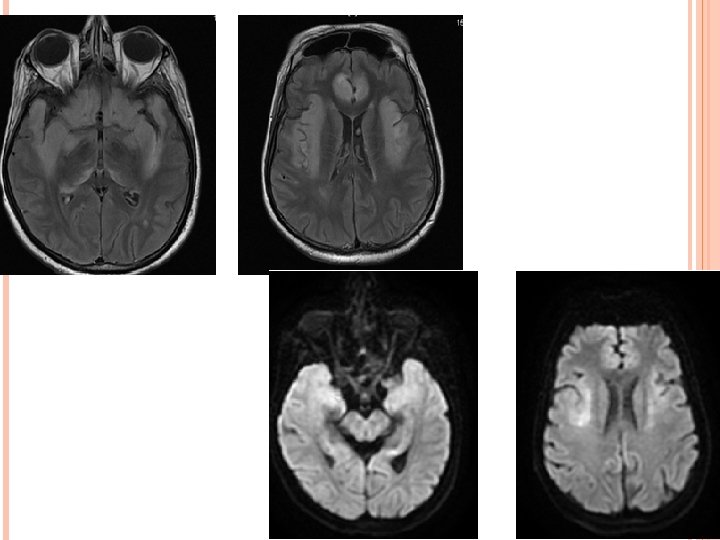

HIV ENCEPHALITIS NECT- Normal or atrophy +/- WM hypodensity. MR • • • v Volume loss with prominent sulci and ventricle. T 2/FLAIR hazy symmetric WM hyperintensity, spare the subcortical U fibers. No mass effect. Usually no enhancement and no restricted diffusion. T 1 images reveal no hypointensity. Reduced grey matter volume in superior and medial frontal gyri – possible early imaging marker. D/D- PML, CMV enchephalitis, ventriculitis; toxoplasmosis; Herpes and HHV-6 encephalitis.

PROGRESSIVE MULTIFOCAL LEUKOENCEPHALOPATHY • ETIOLOGY- JC virus. Ubiquitous virus. Immunodificiency. Most common predisposing condition = HIV (80%). • Three phases of devlopment. Virus exclusively affect the oligodendrocytes. Multifocal demyelination. Predominantly affect parietal & occipital lobes. posterior fossa white matter and basal ganglia involvement is also present. CNS manifestation are c. PML , i. PML, JC encephalitis/meningitis.

IMAGING: Multifocal WM lesions but may be unifocal. Bilaterally assymetric. Involve subcortical U fibers. Spare cortex. No mass effect/enhancement (except i. PML) On DWI, varies according to disease stage. MRS- Decrease NAA, increased choline and lipid lactate peak. p. MRI – shows reduced r. CBV. D/D- HIVE, PML-IRIS, CMV.